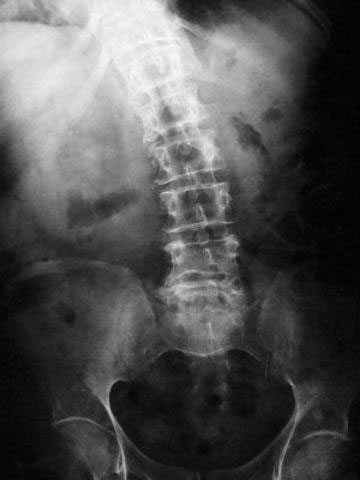

Artrosis lumbar con pinzamiento.

Artrosis lumbar

Escoliosis, artrosis, aplastamiento...